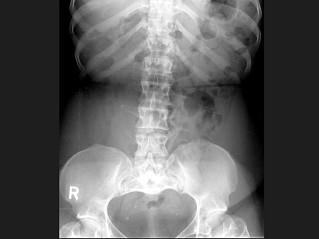

女,41岁,身材矮小,背痛,结合图像,最可能的诊断是?(?)A.腰椎退行性变B.腰椎间盘突出C.软骨发育不全D.石骨症E.马方综合征

问题 女,41岁,身材矮小,背痛,结合图像,最可能的诊断是?(?)

选项 A.腰椎退行性变 B.腰椎间盘突出 C.软骨发育不全 D.石骨症 E.马方综合征

答案 C